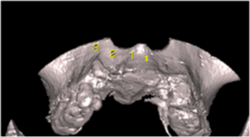

3 D写真

術直後